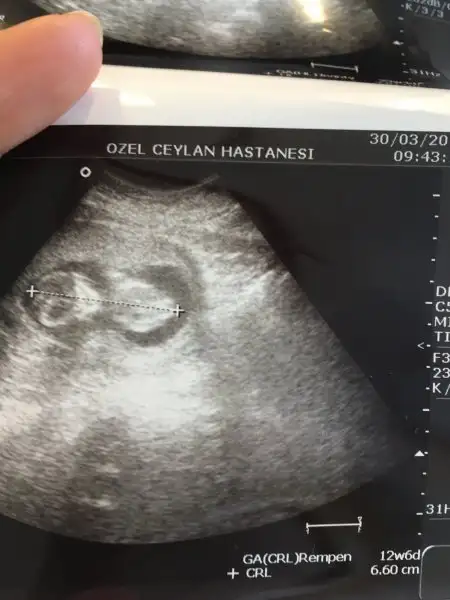

Kozlar bugeve hastanede yatcam ıgne ılac vercekler yatıyorum sadece wc ıcın kalkcaksın dedı dr kanama devam ettıkce dusuk tehdıdım varmıs bebek ıyıydı cok kıprasıyodu ellerı atakları ıns bısı olmazmayrıca gelısımı bıgun onde

benım bebeğimde 5 gün ilerde gidiyor .... İkli tarama testi yaptırdınmı?Bısey olursa acıl mudahale ıcın hastanedeym cnm sabaha cıkcam kısmetse 12+6 gozuktu bebek bıgun ılerden gıdıyo ıns bısey olmaz